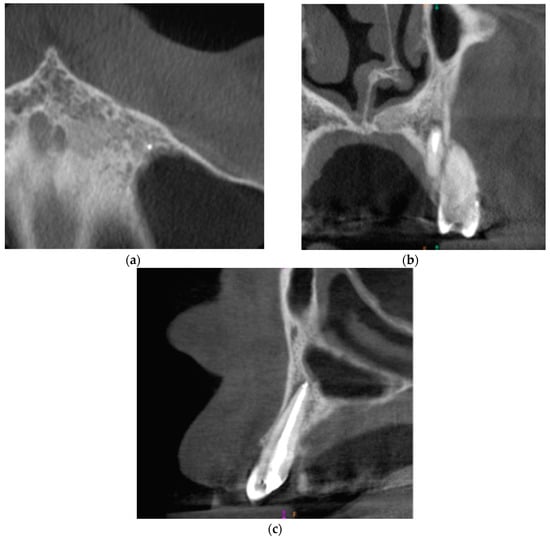

The CBCT of tooth 23 was taken. The periapical lesion was also measured with the use of CS 3D Imaging v3.5.18 Software (Carestream Health Inc., Trophy, Croissy-Beaubourg, France). The measured dimensions of the lesion were 12.7 × 8.7 × 6.4 mm. The CBCT images of the periapical lesion are presented in Figure 5.

Figure 5. Preoperative CBCT images presenting the periapical lesion around the root of tooth no. 23 (date of CBCT examination: 19 January 2021): (a) axial view; (b) coronal view; and (c) sagittal view.